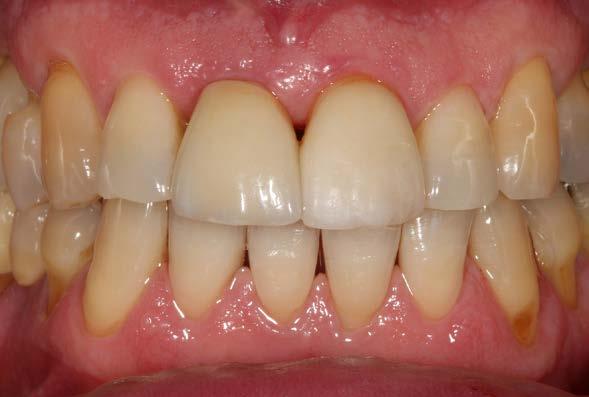

Pasados estos 3 días, podemos colocar la corona provisional de carga inmediata, habiéndose generado

Figuras

ya cicatrización parcial del tejido blando. Estando en esta fase de cicatrización temprana, podemos además adaptar los tejidos blandos a la emergencia que queremos darle al incisivo central (Figura 12 y 13 ). La prótesis provisional se mantiene durante 3 meses. Transcurrido este tiempo se confecciona sobre el mismo transepitelial la prótesis definitiva. De esta manera, las uniones epiteliales formadas entre el tejido gingival periimplantario y el transepitelial no se rompen, garantizándose un mejor sellado a este nivel, evitándose problemas como la mucositis periimplantaria. El paciente continúa en seguimiento posterior durante 2 años. En las imágenes clínicas se observa la estabilidad de los tejidos blandos (Figura 14 y 15). En este momento del seguimiento se realiza un nuevo cone-beam en el que vemos la anchura lograda a nivel crestal, con una regeneración completa de la tabla vestibular (Figura 16).

Figuras 12 y 13. Colocación de la prótesis provisional de carga inmediata a los tres días de la cirugía. Podemos ver en las imágenes como el contorno gingival se ha podido recrear con exactitud al encontrarse en una fase temprana de la cicatrización.

el mismo transepitelial, realizando una prótesis provisional sobre interfase (del mismo modo que si fuese definitiva) sin romper la unión implante-tejido blando en la zona crítica ha podido marcar la diferencia en cuanto a la conservación del tejido blando periimplantario y, por lo tanto, también del hueso crestal adyacente. El manejo del gap es otro punto diferencial en el éxito a largo plazo del implante inmediato, como

hemos explicado anteriormente. En nuestro caso, el uso de PRGF-Endoret para rellenarlo ha generado un hueso estable, como hemos podido evidenciar en el tac de control a los 2 años, así como evitar la reabsorción de la tabla vestibular, hecho clave en la zona estética. Existen numerosas referencias en la literatura internacional en los que se ha puesto a prueba el potencial del PRGF-Endoret como regenerador del alveolo

Figuras 14 y 15. Estado de los tejidos blandos 2 años después de la colocación de la prótesis definitiva.

Figura 16. Comparativa inicial y final a los 2 años del seguimiento con la regeneración completa de la tabla vestibular y el mantenimiento tras la carga.